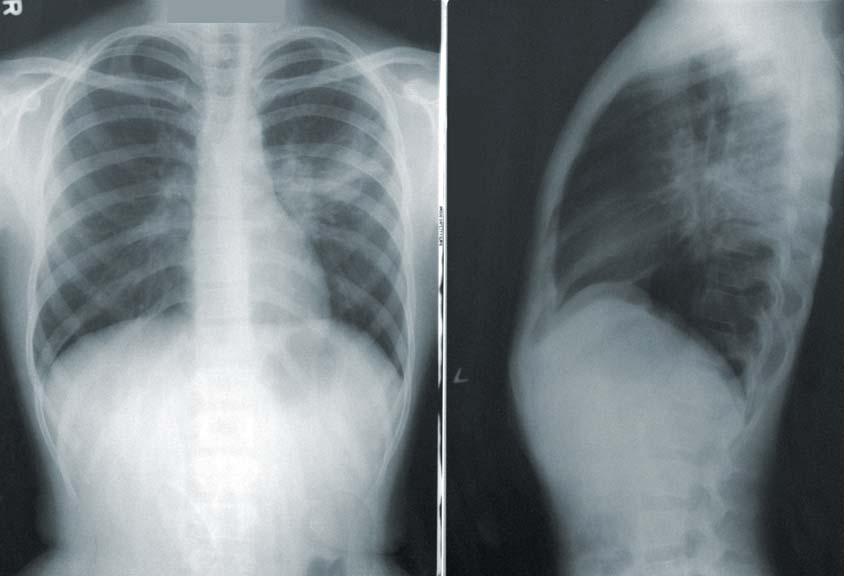

나. 폐암 검진: 폐암을 조기에 발견하기 위해 폐초음파, 폐촬영(CT 또는 X-레이), 체위 선별검사 등의 검진을 받을 수 있습니다.